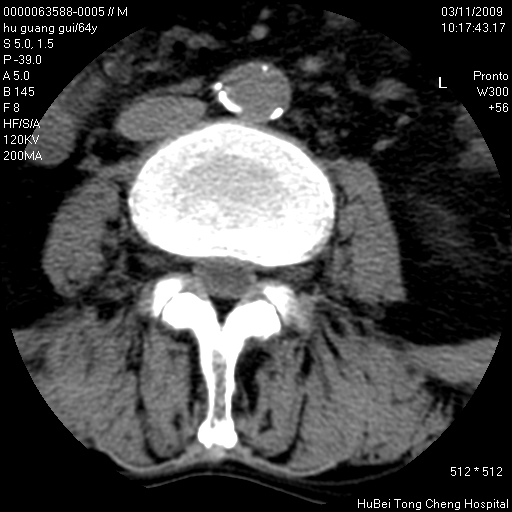

患者 男,64岁。腰痛十余天。(临床未提供其他病史)

临床诊断:腰痛原因待查(腰椎间盘突出症?)。

腰椎间盘ct轴位平扫(层厚5mm,层距4mm),图像如下:

腰椎退行性变,腰4—5椎间盘膨出。

右侧骶骨侧块骨侵蚀,骶髂关节骨性关节面破坏,并见软组织肿块,考虑骨转移瘤可能,进一步检查。

1.腰椎退行性变,腰4—5椎间盘膨出。

2.右侧骶骨侧块骨侵蚀,骶髂关节骨性关节面破坏,并见软组织肿块,考虑:脊索瘤,骨转移瘤可能,进一步检查。

1)腰椎退行性变,l4—5椎间盘膨出。2)骶骨右侧块骨转移瘤可能,3)水平骶椎。建议作一步检查。